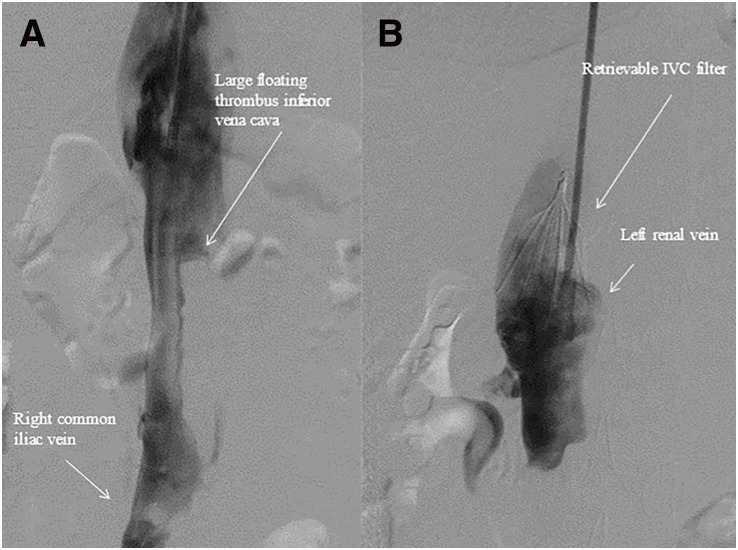

抗磷脂综合征(APS)和系统性红斑狼疮(SLE)相似,其特征是血栓栓塞事件和多种临床表现。我们经历了一个21岁的男性急性髂腔深静脉血栓形成(DVT)。原发性APS初步诊断符合标准,经多学科治疗,髂腔DVT逐渐消退。6个月后,患者主诉急性肠炎,接着是周围神经病变和蝴蝶狼疮。诊断为SLE,提示SLE发病前有APS。这个病例提出了一个问题,目前的共识,这两种疾病是明显不同的临床实体,尽管它们是密切相关的。

Antiphospholipid syndrome (APS) and systemic lupus erythematosus (SLE) are similar to be characterized by thromboembolic events and various clinical manifestations. We experienced a 21-year-old man with acute iliocaval deep vein thrombosis (DVT). Primary APS was initially diagnosed on the criteria, and after multidisciplinary treatment, iliocaval DVT was gradually regressed. Six months later, the patient complained of acute enteritis, followed by peripheral neuropathy and butterfly lupus. SLE was diagnosed, which suggested that the onset of SLE was preceded by APS. This case raises the question of a present consensus that these two diseases are clearly different clinical entities, although these are closely related.